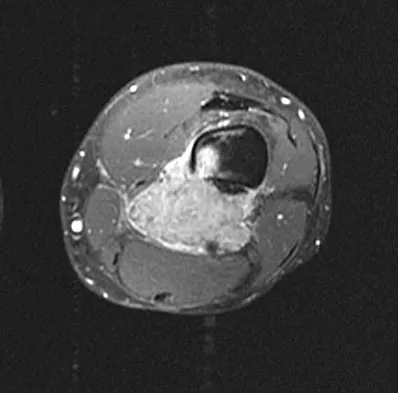

Figure 22 shows the MRI scan of a 20-year-old female basketball player who has pain over the anterior knee that interferes with her performance. Examination reveals phase III Blazina patellar tendinosis. Management should consist of

Excision of the affected mucoid degenerative area is considered appropriate management in the Blazina classification system. A finding of phase III indicates persistent pain with or without activities, as well as deterioration of performance. With the appearance of the mucoid degeneration and the vigorous activity level of the intercollegiate basketball player, it is unlikely that nonsurgical management will provide adequate relief. When excising the affected degenerative area, care must be taken to retain normal tendon fibers. The defect in the patellar tendon is closed with absorbable sutures, as is the paratenon. Postoperative rehabilitation involves initial mobilization extension, with progressive range-of-motion and mobilization exercises as tolerated and weight bearing as tolerated. Open chain and isokinetic exercises are delayed until full range of motion and mobility is obtained, generally within 4 weeks. A return to activities is achieved by 80% to 90% of athletes, although there may be occasional activity-related aching for 4 to 6 months after surgery. Blazina ME, et al: Jumper's knee. Orthop Clin North Am 1973;4:665. Kelly DW, Carter VS, Jobe FW, Kerlan RK: Patellar and quadriceps tendon ruptures: Jumper's knee. Am J Sports Med 1984;12:375-380. Krums PE, Ryder B: Operative treatment of patella tendon disorders. Operative Techniques Sports Med 1994;2:303.